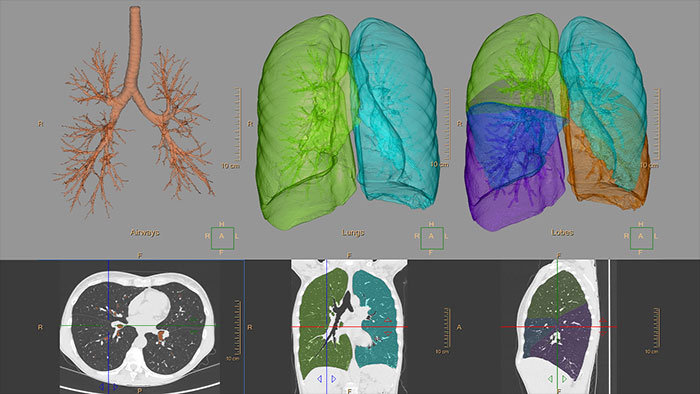

COPD

CT COPD

Quantify diffuse lung disease

CT COPD helps visualize and quantify the destructive process of diffuse lung disease (e.g. emphysema). The application provides a guided workflow for airway analysis, reviewing and measuring airway lumen, and assessing air trapped.

Benefits

• Automatic lung and lobes segmentation.

• Automatic airway extraction, airway tree segmentation and navigation path extraction, enabling the measurement of airway parameters such as lumen diameter and wall cross-section.

• Tools for qualitative and quantitative temporal comparison of up to four follow-up studies in order to determine the progression of the disease.